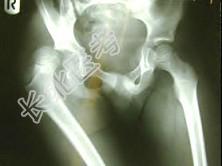

- [材料题] 男,44岁,因外伤右髋痛12小时。查体:生命体征平稳,右下肢短缩,髋关节屈曲,内收,内旋畸形。请结合所提供的图像,进行选择:

- 多项选择题1.此患者应诊断为 ( )

A、右髋前脱位

B、右髋后脱位

C、右髋中心脱位

D、右股骨颈骨折

E、右髋臼骨折

F、右髋内旋脱位

- 多项选择题2.应选择的治疗方法 ( )

A、Allis法

B、Knowles针

C、Ender杆

D、Braun架

E、Thomas架

F、Schanz针